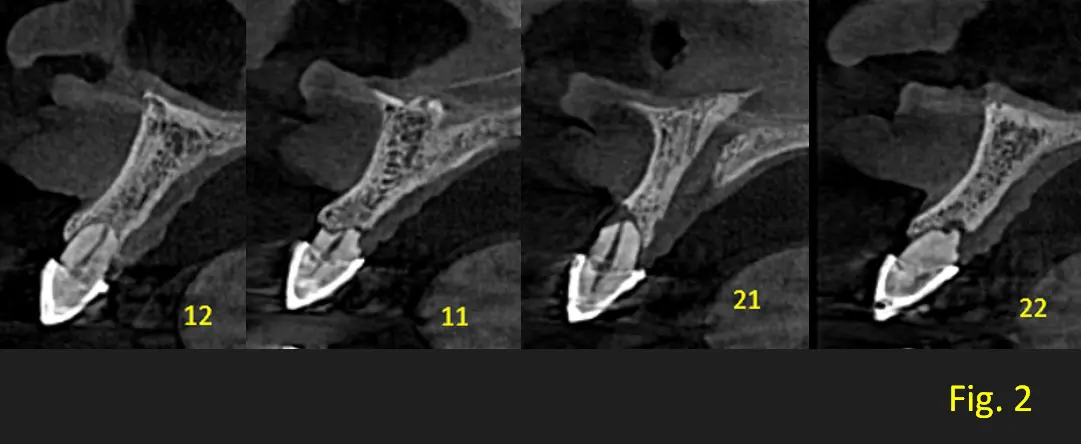

En una vista panoramica se observa que los apices de los incisivos centrales y laterales presentan una forma redondeada y corta. Pieza dentaria 2.1 presenta proceso de reabosción debido a que sigue con los patrones rectos y marcados como podemos visualizar en los cortes transaxiales (ver Fig. 1 y 2). Signos radiograficamente compatibles con Displasia dentinaria tipo 1.